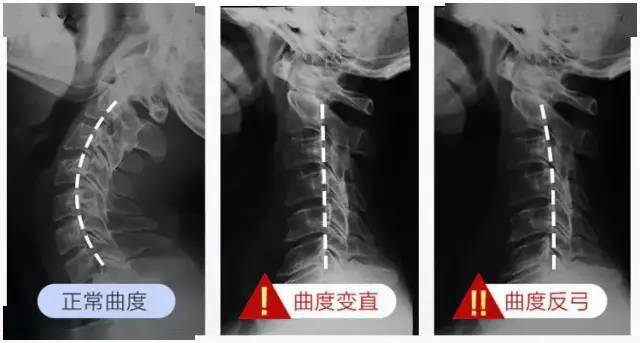

如果你看得这里 , 那请记住了:颈椎本身就是弯的 , 直的颈椎才是真正的病变!